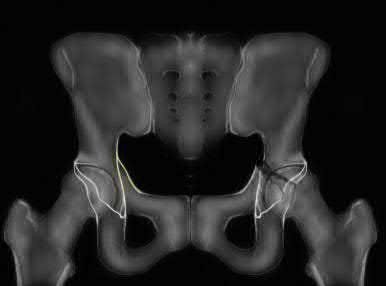

Question 11:

A poly-trauma patient presents hemodynamically unstable with an anteroposterior compression (APC-III) pelvic ring injury. A circumferential pelvic binder is requested to reduce pelvic volume and control hemorrhage. To be anatomically effective, the binder must be centered precisely over which of the following landmarks?

Correct Answer: Greater trochanters

Explanation:

For optimal mechanical advantage and effective reduction of an 'open book' pelvic fracture (APC type), a pelvic binder must be applied directly over the greater trochanters of the femurs. Applying it higher, such as over the iliac crests, is a common error that fails to adequately close the pelvic ring and can paradoxically open the true pelvis.